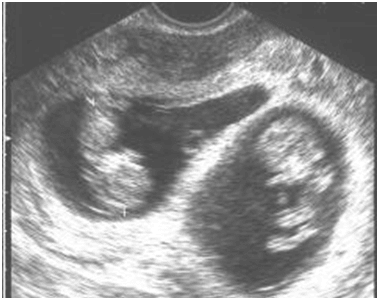

Hej kobietki!Ja już po usg. Jest wszystko ok, maluchy rosną a co mnie bardzo cieszy są dwie owodnie jednak. Jedno dzieciątko jest troszke mniejsze i mnie to martwi ale ponoć jeszcze może podskoczyć. No i wstawiam obiecaną fotke.

Zobacz załącznik 395309